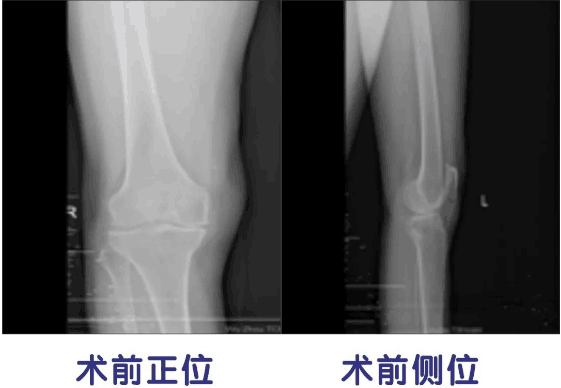

近日,梧州市中医医院下肢骨关节二科成功实施梧州市首例人工膝关节单髁置换术,解决了59岁老奶奶多年的疼痛困扰,术后经过康复功能锻炼,康复良好,现可独立行走。据悉,该手术的成功,不仅填补了梧州市骨科领域的技术空白,同时也标志我院在人工膝关节置换技术方面又上了一个新台阶。

患者王某,因长期患者右膝关节疼痛,每天上下楼梯时,疼痛就会加重,严重影响日常生活。在辗转多家医院就诊后,经保守治疗多年无效果,于近期在家人陪伴下来到来我院下肢骨关节二科就诊,经检查发现,右膝关节以内侧胫股间室病变为主,采用全膝关节表面置换术会令其失去正常外侧胫股间室和髌股间室的骨与软骨和前后交叉韧带,手术创伤过重,力学机制改变较大。

大骨科主任邓振中主任医师及其医疗团队经过反复讨论,为王某制定了“右膝关节单髁置换术”的手术方案,即仅对病变的内侧胫股间室进行表面置换,保留全部的交叉韧带和其余间室的软骨面,取得预期效果。患者术后第二天可自由上落楼梯行走。